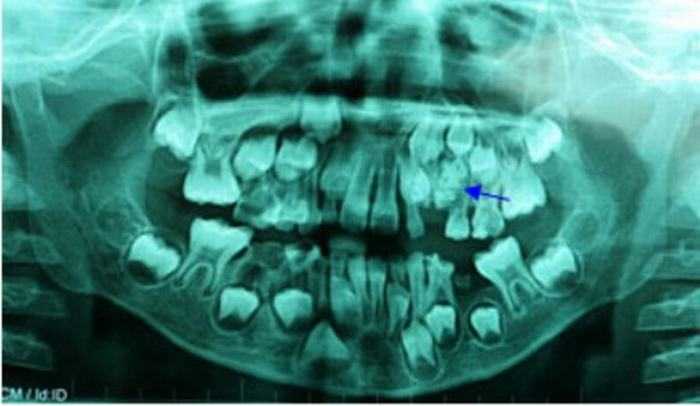

Do mắc phải căn bệnh u răng kết hợp phức tạp nên cậu thanh niên Ashik Gavai, 17 tuổi, người Ấn Độ có tới 232 chiếc răng lớn nhỏ khác nhau mọc chen chúc ở hàm dưới.